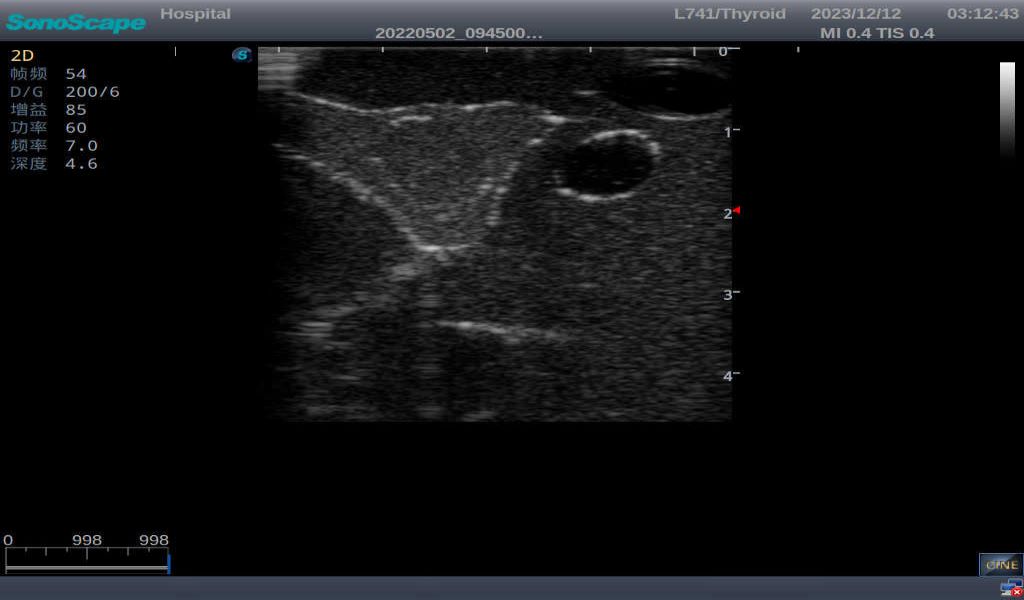

Thyroid Ultrasound Training Model

This product has true-to-life male torso including head, neck, shoulder and upper chest. It serves as an excellent teaching tool for identification of various types of normal thyroid, thyroid adenoma, thyroid cancer, nodular goiter, thyroid cyst and training on proper thyroid scanning techniques.

2)       Ultrasonically realistic materials at neck & various types of real ultrasonic machines in clinical available, developing realistic imaging like common carotid artery, internal jugular vein, trachea, thyroid cartilage, cricoid cartilage, lobes of thyroid gland and isthmus

3)       It comes with four (4) thyroid modules and can show five (5) ultrasonic images: normal thyroid, thyroid adenoma, thyroid cancer, nodular goiter, thyroid cyst

Thyroid cyst, which fluid area, dark and echo-free area can be seen